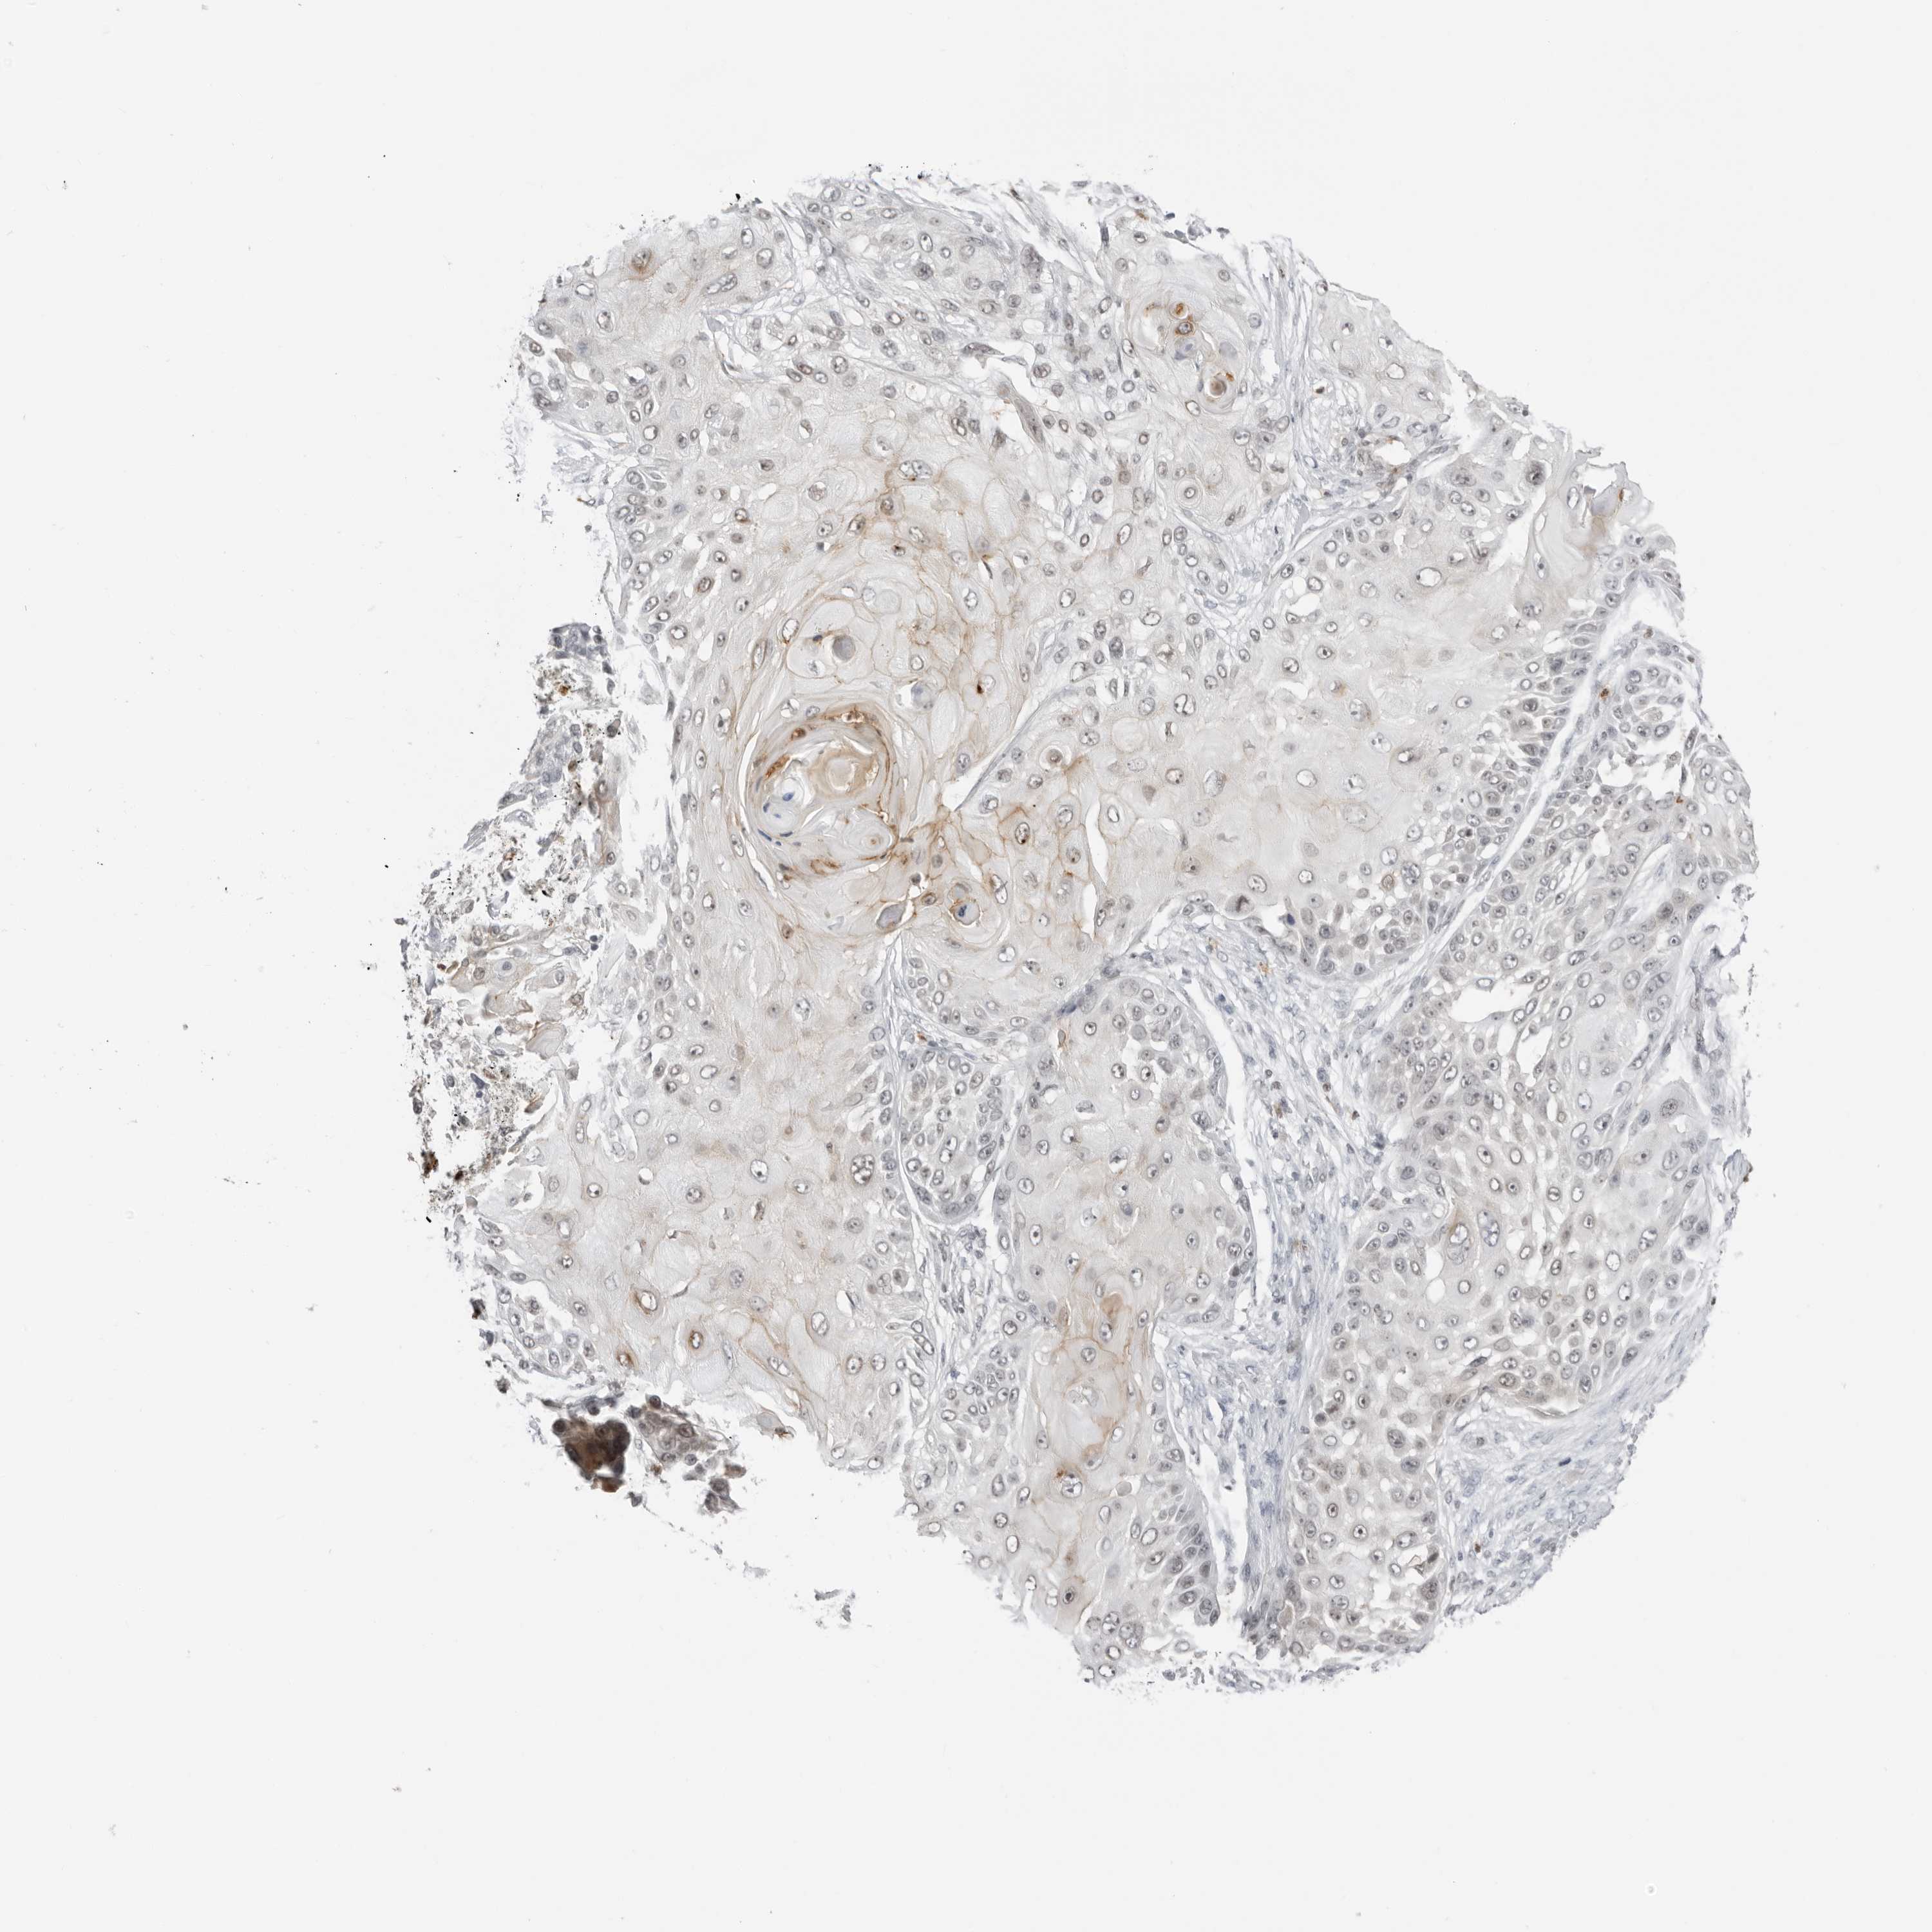

SKIN CANCER - Protein expressioni

A mouse-over function shows sample information and annotation data. Click on an image to view it in a full screen mode. Samples can be filtered based on level of antibody staining by selecting one or several of the following categories: high, medium, low and not detected. The assay and annotation is described here.

Antibody staining in the annotated cell types in the current human tissue is reported as not detected, low, medium, or high, based on conventional immunohistochemistry profiling in selected tissues. This score is based on the combination of the staining intensity and fraction of stained cells.

Each image is clickable and will lead to virtual microscopy that enables deeper exploration of all samples and also displays staining intensity scores, fraction scores and subcellular localization as well as patient and tissue information for each sample.

Antibody HPA027158

Antibody HPA027209

Basal cell carcinoma

Squamous cell carcinoma, NOS

Squamous cell carcinoma, metastatic, NOS